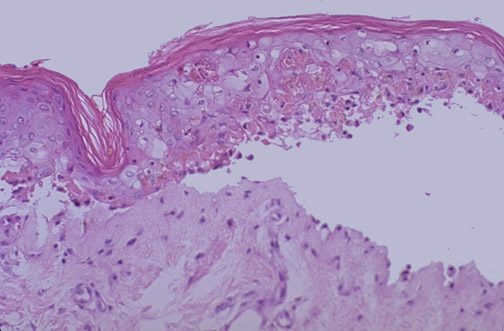

| There are few dermatologic emergencies. This is one of them known as toxic epidermal necrolysis, or TEN. Seen here is a necrotic epidermis lifting off the dermis to form a subepidermal bulla. There are several variations on this theme, which may be the result of a reaction inducing keratinocyte apoptosis as a consequence of an infection or use of a drug: |